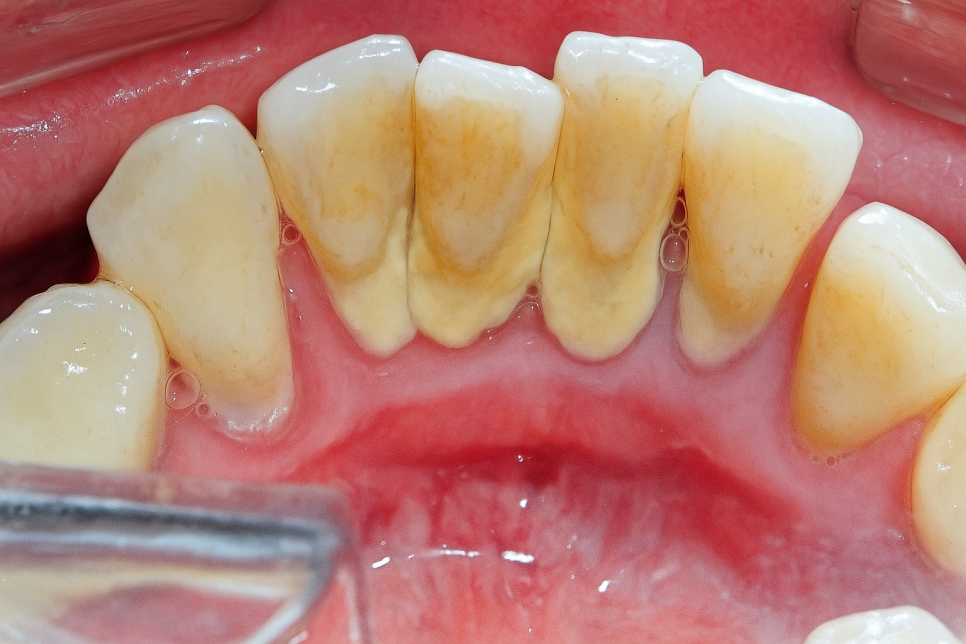

치아 사이 틈은 매우 긴밀합니다.

그래서 칫솔모가 여기까지 닿지 않아 치실이나 치간 칫솔을 써야 되는데,

만약 이 사이가 관리되지 못해 음식 찌꺼기가 오랫동안 껴 있으면

인접면 우식증 즉, 치아 사이도 썩을 수 있습니다.

눈으로 잘 안 보이는 곳이라 초기에 발견하기 어려우며,

대개 깊게 진행되어 통증을 느낀 후 문제가 있음을 깨닫게 됩니다.

그런데 문제는 이 사이(인접면)은

음식을 씹을 때 사용하는 교합면과 달리

겉질이 얇아 안쪽 속질까지 빠르게

이가 썩어들어간다는 점입니다.

또한 눈에 잘 안 보이기 때문에 초기에 발견하더라도

기구가 닿을 수 있도록 멀쩡한 치아를 많이 삭제해야 되므로

미리 예방하는 것이 정말 중요하죠.